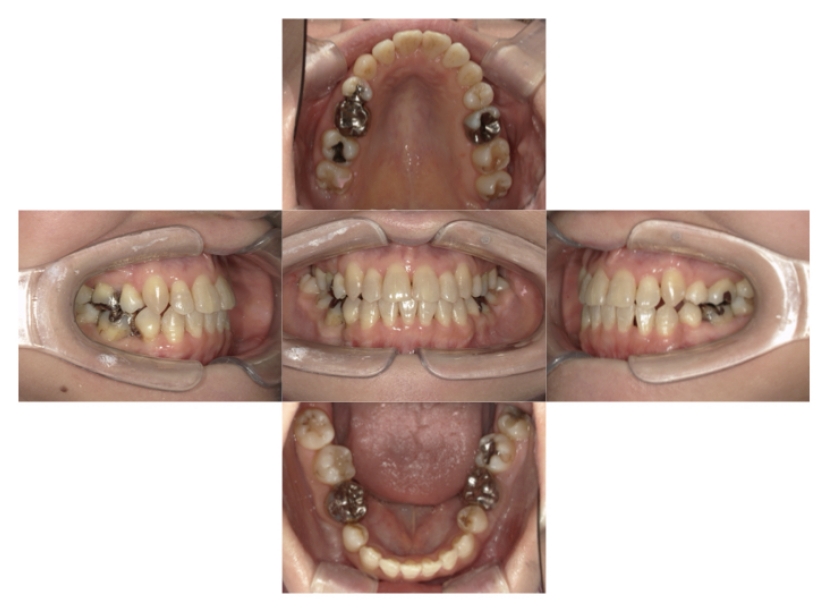

BEFORE

AFTER

上下顎叢生、上顎前突(出っ歯、上下の前歯のガタガタ)のケースです。

装置はラビアル(上下表側)で、上顎の小臼歯を2本抜歯を行っています。抜歯したスペースを使って、上の前歯の後方移動と叢生(ガタガタ)と出っ歯の改善を行っています。下は歯と歯の間にIPR(隣接面削合)を行い、スペースを確保し、叢生の改善を行っています。

主訴 前歯のガタガタと出っ歯が気になる。

年齢・性別 47歳 女性

お住まいの地域 神奈川県川崎市

治療方針 抜歯スペースおよびIPRを利用して上前歯の叢生(ガタガタ)の改善

抜歯部位 上顎左右第一小臼歯

使用装置 ラビアル(上下表側)、顎間ゴム

治療期間 2年0か月

治療回数 15回

リテーナー クリアリテーナー